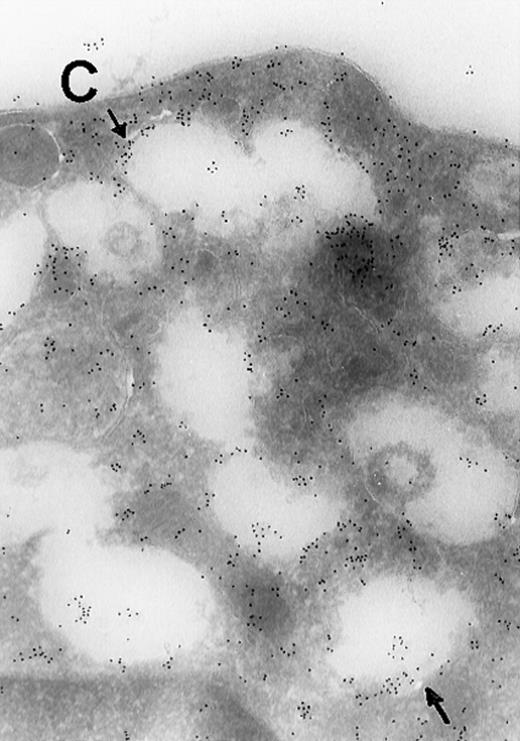

In view of these reports, we determined the cellular localization of MAP kinase in megakaryocytes, with a particular attention to the platelet-yielding demarcation membranes.7As a control, we determined the localization of another TPO-upregulated serine/threonine kinase, Mst1.8 Our current Electron Microscopic (EM) studies, performed as we described before,9 reveal that a significant fraction of MAP kinase, but none of Mst1, localizes to the demarcation membranes. In resting platelets, MAP kinase is found in a cluster pattern associated with the plasma membrane (which is believed to originate from the megakaryocytic demarcation membranes),7 as well as over electron-dense cytoplasmic domains (Figure). In view of our finding that MAP kinase is localized to the demarcation membranes in megakaryocytes, it is of interest to note that this kinase was also shown to be localized in Golgi membranes and involved in their fragmentation during mitosis in a microtubule-dependent manner.10 Platelet fragmentation likely involves the cytoskeleton, and perhaps MAP kinases are also involved in this process.

(A) Ultrathin frozen sections of rat platelets immunolabeled with antibodies to ERK (magnification ×45 000). (B) Well-developed demarcation membranes in a rat (Wistar), TPO-treated megakaryocyte7 9 immunostained with an antibody to Mst1 (magnification ×48 000), or (C) with an antibody to ERK, which recognizes ERK1 and ERK2 (magnification ×65 400). The arrows point to the demarcation membranes. The Mst1 antiserum (gift of Dr Jonathan Chernoff, Fox Chase Cancer Center, Philadelphia, PA) and anti-ERK2 (K-23) (Santa Cruz Biotechnology, Santa Cruz, CA) or TR2, anti-ERK (gift of Michael Weber, University of Virginia Medical School) were diluted 1:10.

(A) Ultrathin frozen sections of rat platelets immunolabeled with antibodies to ERK (magnification ×45 000). (B) Well-developed demarcation membranes in a rat (Wistar), TPO-treated megakaryocyte7 9 immunostained with an antibody to Mst1 (magnification ×48 000), or (C) with an antibody to ERK, which recognizes ERK1 and ERK2 (magnification ×65 400). The arrows point to the demarcation membranes. The Mst1 antiserum (gift of Dr Jonathan Chernoff, Fox Chase Cancer Center, Philadelphia, PA) and anti-ERK2 (K-23) (Santa Cruz Biotechnology, Santa Cruz, CA) or TR2, anti-ERK (gift of Michael Weber, University of Virginia Medical School) were diluted 1:10.